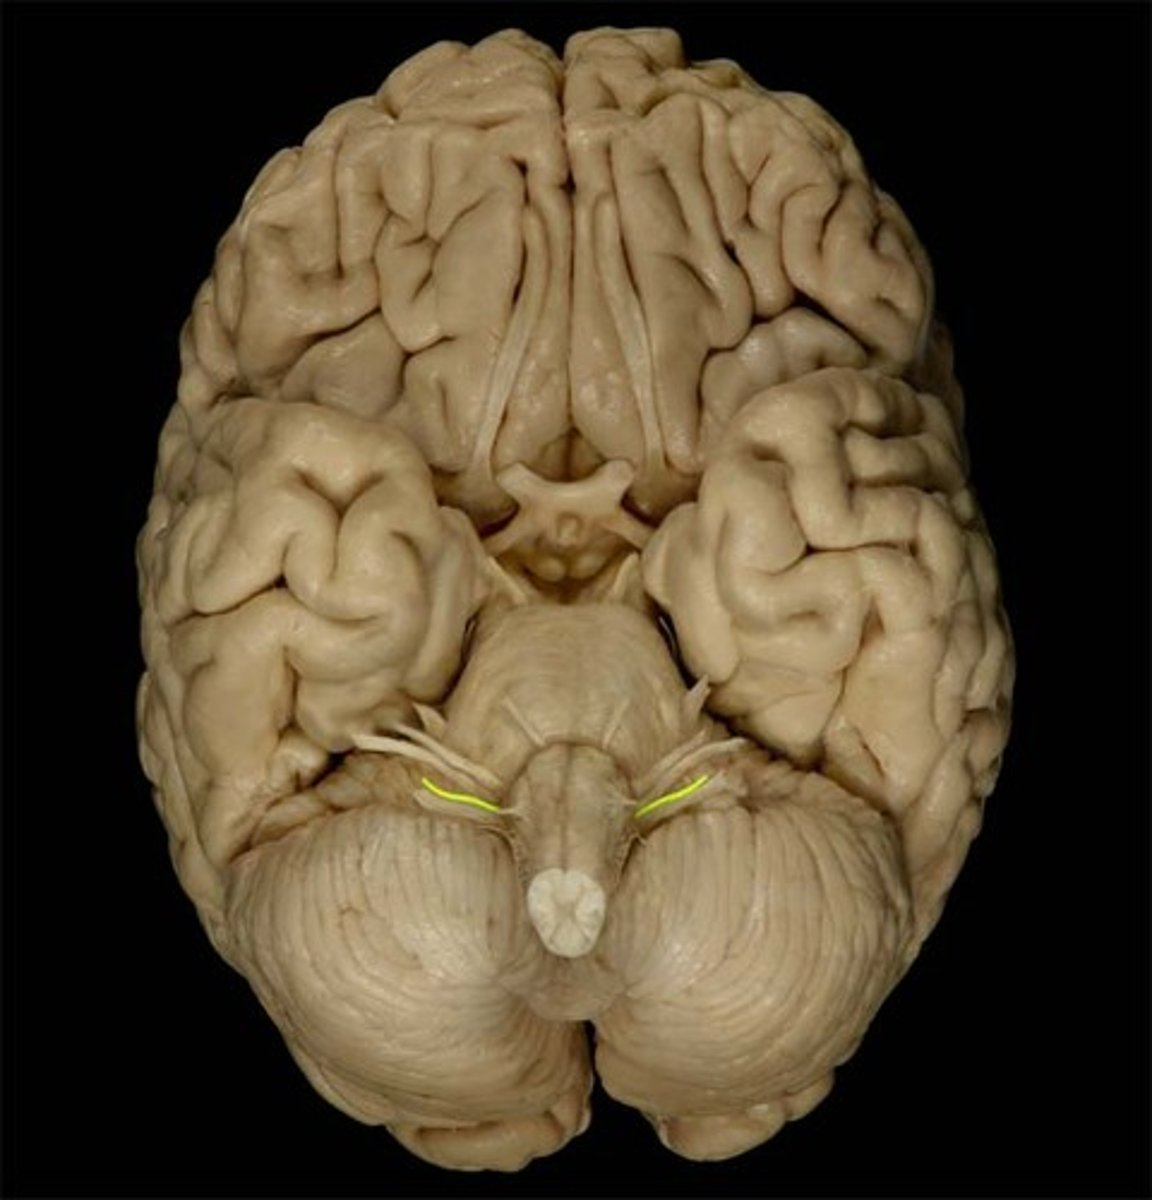

Glossopharyngeal Nerve

Function: mixed (motor, parasympathetic, visceral sensory, general sensory)- taste on posterior of tongue, gag reflex, swallowing

Location: Medulla

Vagus Nerve

Function: mixed (motor, parasympathetic, visceral sensory, general sensory)- visceral muscle movement (heart, lungs, intestines)